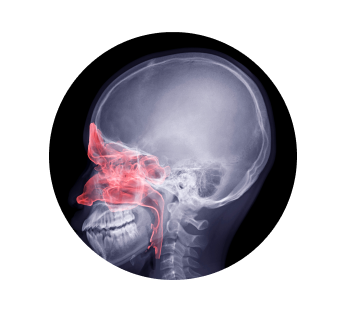

Рентген пазух носа – это диагностическая процедура, которая позволяет эффективно визуализировать придаточные пазухи и кости лицевой части головы в носовой области. За счет высокого уровня точности возможна идентификация даже мельчайших патологий. Во время исследования пациент не испытывает дискомфорта и болевых ощущений. Изучению подвергается не только костная ткань, но также мягкие ткани и анатомические полости. В полученном заключении можно будет найти всю информацию о состоянии носовой области и пазух – патологии развития, аномалии функционирования, а также искривления и травмы.

Как проходит рентген пазух носа

В нашем медицинском центре оборудован комфортный диагностический кабинет с новейшим оборудованием прецизионного уровня точности. Перед тем, как разместиться в сканере необходимо снять все посторонние предметы, способные генерировать помехи – ювелирные украшения, очки, часы и т.д. На верхнюю часть тела помещается специальный свинцовый фартук, который защитит от избыточного излучения. Врач находится в соседней комнате, общаясь с пациентом по громкой связи. Все снимки транслируются на экран в режиме онлайн.

Рентген придаточных пазух носа выполняется в четырех плоскостях. Положение тела менять не нужно – пациент сидит на специальном стуле, голова помещена в фиксатор. Врач самостоятельно меняет положение рентгеновского датчика.

• Подбородочно-черепной снимок – визуализирует лобную пазуху и клиновидную кость;

• Задне-передний снимок – визуализируют лобную и решетчатую пазухи;

• Боковой снимок – визуализирует верхнечелюстную, лобную и клиновидную пазухи;

• Снимок в позиции Уотерса – визуализирует фронтальную часть решетчатой пазухи, а также дно глазниц.